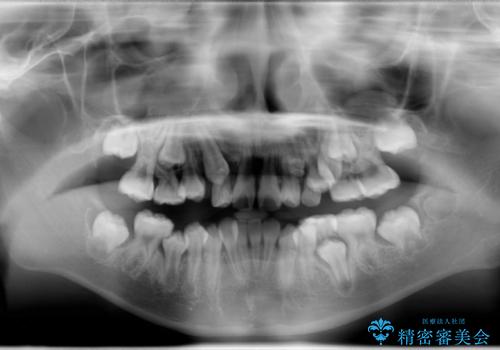

- 乳歯の晩期残存による永久歯の萌出遅延・過剰歯・萌出異常

など多くの問題を抱えていた。

過剰歯と乳歯を抜歯後、リンガルアーチを用いて大まかな移動を行った後、マルチブラケットへ移行し、可及的に正常咬合へと誘導することを試みた。

乳歯がうまく抜けず、過剰歯が存在していたことにより、永久歯が位置異常をおこし、非常に複雑な状況となってしまっていました。

乳歯・過剰歯を除去し、リンガルアーチを用いて埋伏していた犬歯を牽引、その他おおまかな動きを行った後、マルチブラケットにて永久歯の咬合を誘導しました。